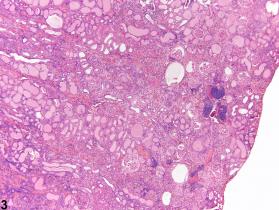

Early lesions consist of focal to multifocal foci of tubule basophilia, nuclear crowding, peritubular basement membrane thickening, and variable infiltration by mononuclear inflammatory cells (Figure 1). As the disease progresses, the amount of affected renal parenchyma increases, individual components of CPN become more severe, and hyaline casts are prominent (Figure 2 and Figure 3). At the same time, glomerular changes, such as capillary tuft thickening, adhesions between the glomerular epithelium and Bowman’s capsule, and glomerulosclerosis, may be evident. CPN may progress to end-stage kidney disease, resulting in the death of the animal (Figure 4). CPN can often be exacerbated by chemical administration. The incidence and severity of CPN are generally less in the mouse than in the rat (Figure 5).

Kidney - Nephropathy, Chronic progressive in a male F344/N rat from a subchronic study. The early cases of chronic progressive nephropathy (CPN) occur as focal to multifocal areas of tubule basophilia with or without hyaline (protein) casts.